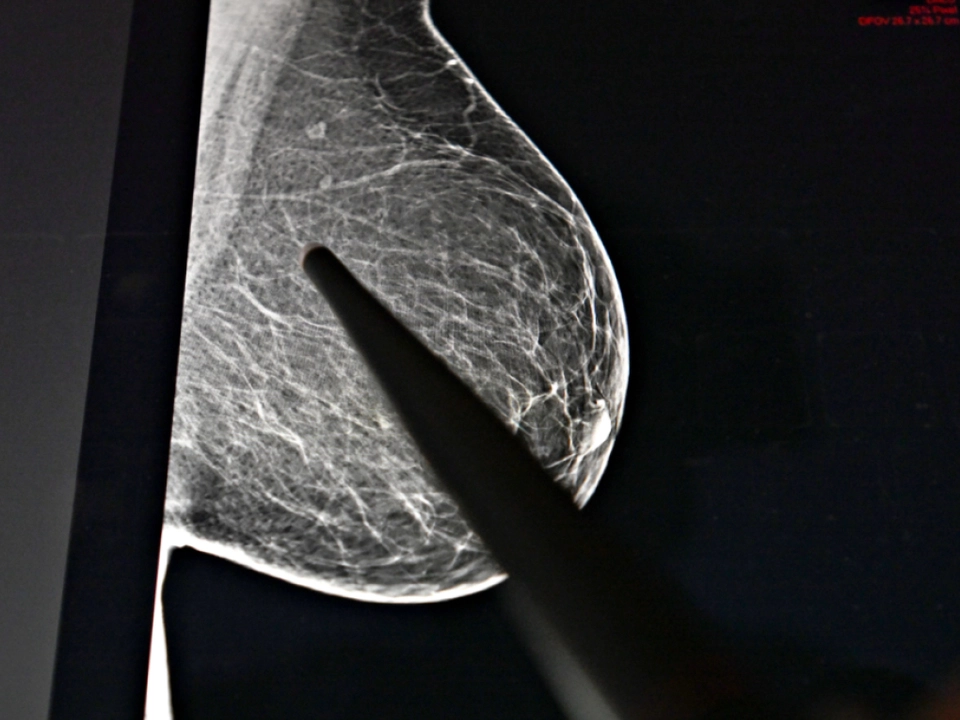

Brustkrebs bei Frauen Nummer eins

Zwischen 2014 und 2024 stieg die Zahl der jährlichen Krebsneuerkrankungen von 41.529 auf 48.360 deutlich an, während das individuelle, altersstandardisierte Erkrankungsrisiko im selben Zeitraum mit 500,8 gegenüber 497,4 je 100.000 Personen nahezu unverändert blieb. 2024 erhielten in Österreich 22.363 Frauen und 25.997 Männer eine Krebsdiagnose. Die häufigsten Diagnosen waren bösartige Tumore der Brust bei Frauen (6.959 Fälle) und bösartige Tumore der Prostata bei Männern (8.152 Fälle), gefolgt von bösartigen Tumoren der Lunge (5.533 Fälle, beide Geschlechter zusammen) und bösartigen Tumoren des Dickdarms bzw. Enddarms (4.769 Fälle, beide Geschlechter zusammen).

Bei Frauen entfielen auf Brustkrebs 2024 rund 31 Prozent der Neuerkrankungsfälle sowie 18 Prozent aller Krebssterbefälle (1.755). Bei Männern war Prostatakrebs mit knapp einem Drittel (31 Prozent) aller 2024 neu diagnostizierten bösartigen Neubildungen und einem Achtel der Sterbefälle (zwölf Prozent) die häufigste Krebsart.